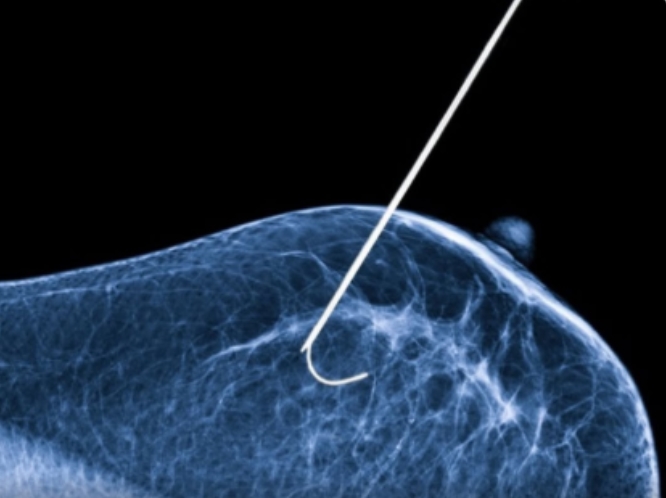

Projeto do Instituto Sociocultural do Hospital de Amor une arte e alegria nos corredores da unidade